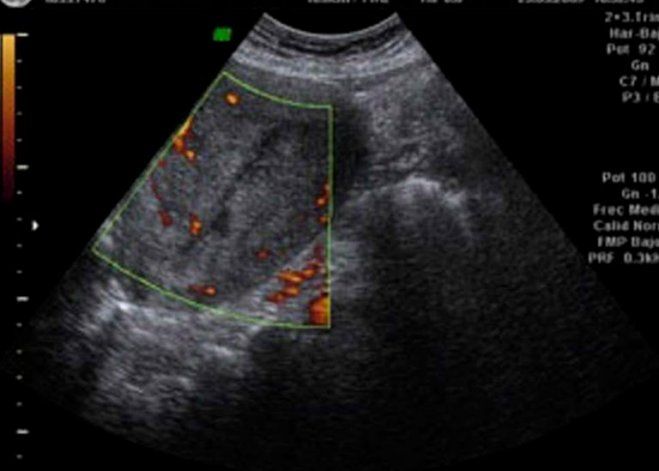

Al mismo tiempo, el experto añadió que aquellos valores están muy por encima de la media en comparación al resto del país: “Particularmente las pérdidas durante el primer trimestre de embarazo crecieron 4,7 veces en esos 22 años”. Por otra parte, agregó: “Es importante destacar que los abortos espontáneos en los primeros tres meses de gestación, son los que en la bibliografía científica están más vinculados a la exposición a tóxicos presentes en el ambiente”.